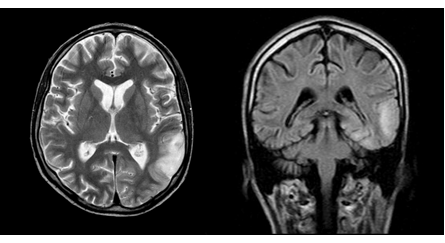

During hospitalization in October 2010, a medical conference was held and a diagnosis was made: chronic herpetic recurrent encephalitis, which must be differentiated from MELAS syndrome (Figure 2).

Figure 2 MRI of the brain in T2 VI and FLAIR modes (September 2010). One can see a center of increased intensity of the MR signal in the cortico-subcortical regions of the left parietal and occipital lobes, a regression of the focus in the right temporal lobe.